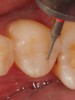

Fig 8. After isolation, a sectional matrix is placed to restore contact and proximal anatomic form to the composite to be placed. The goal is to perform as little rotary finishing and polishing as possible by having the matrix fit precisely to the cavity margins.

Figure 8